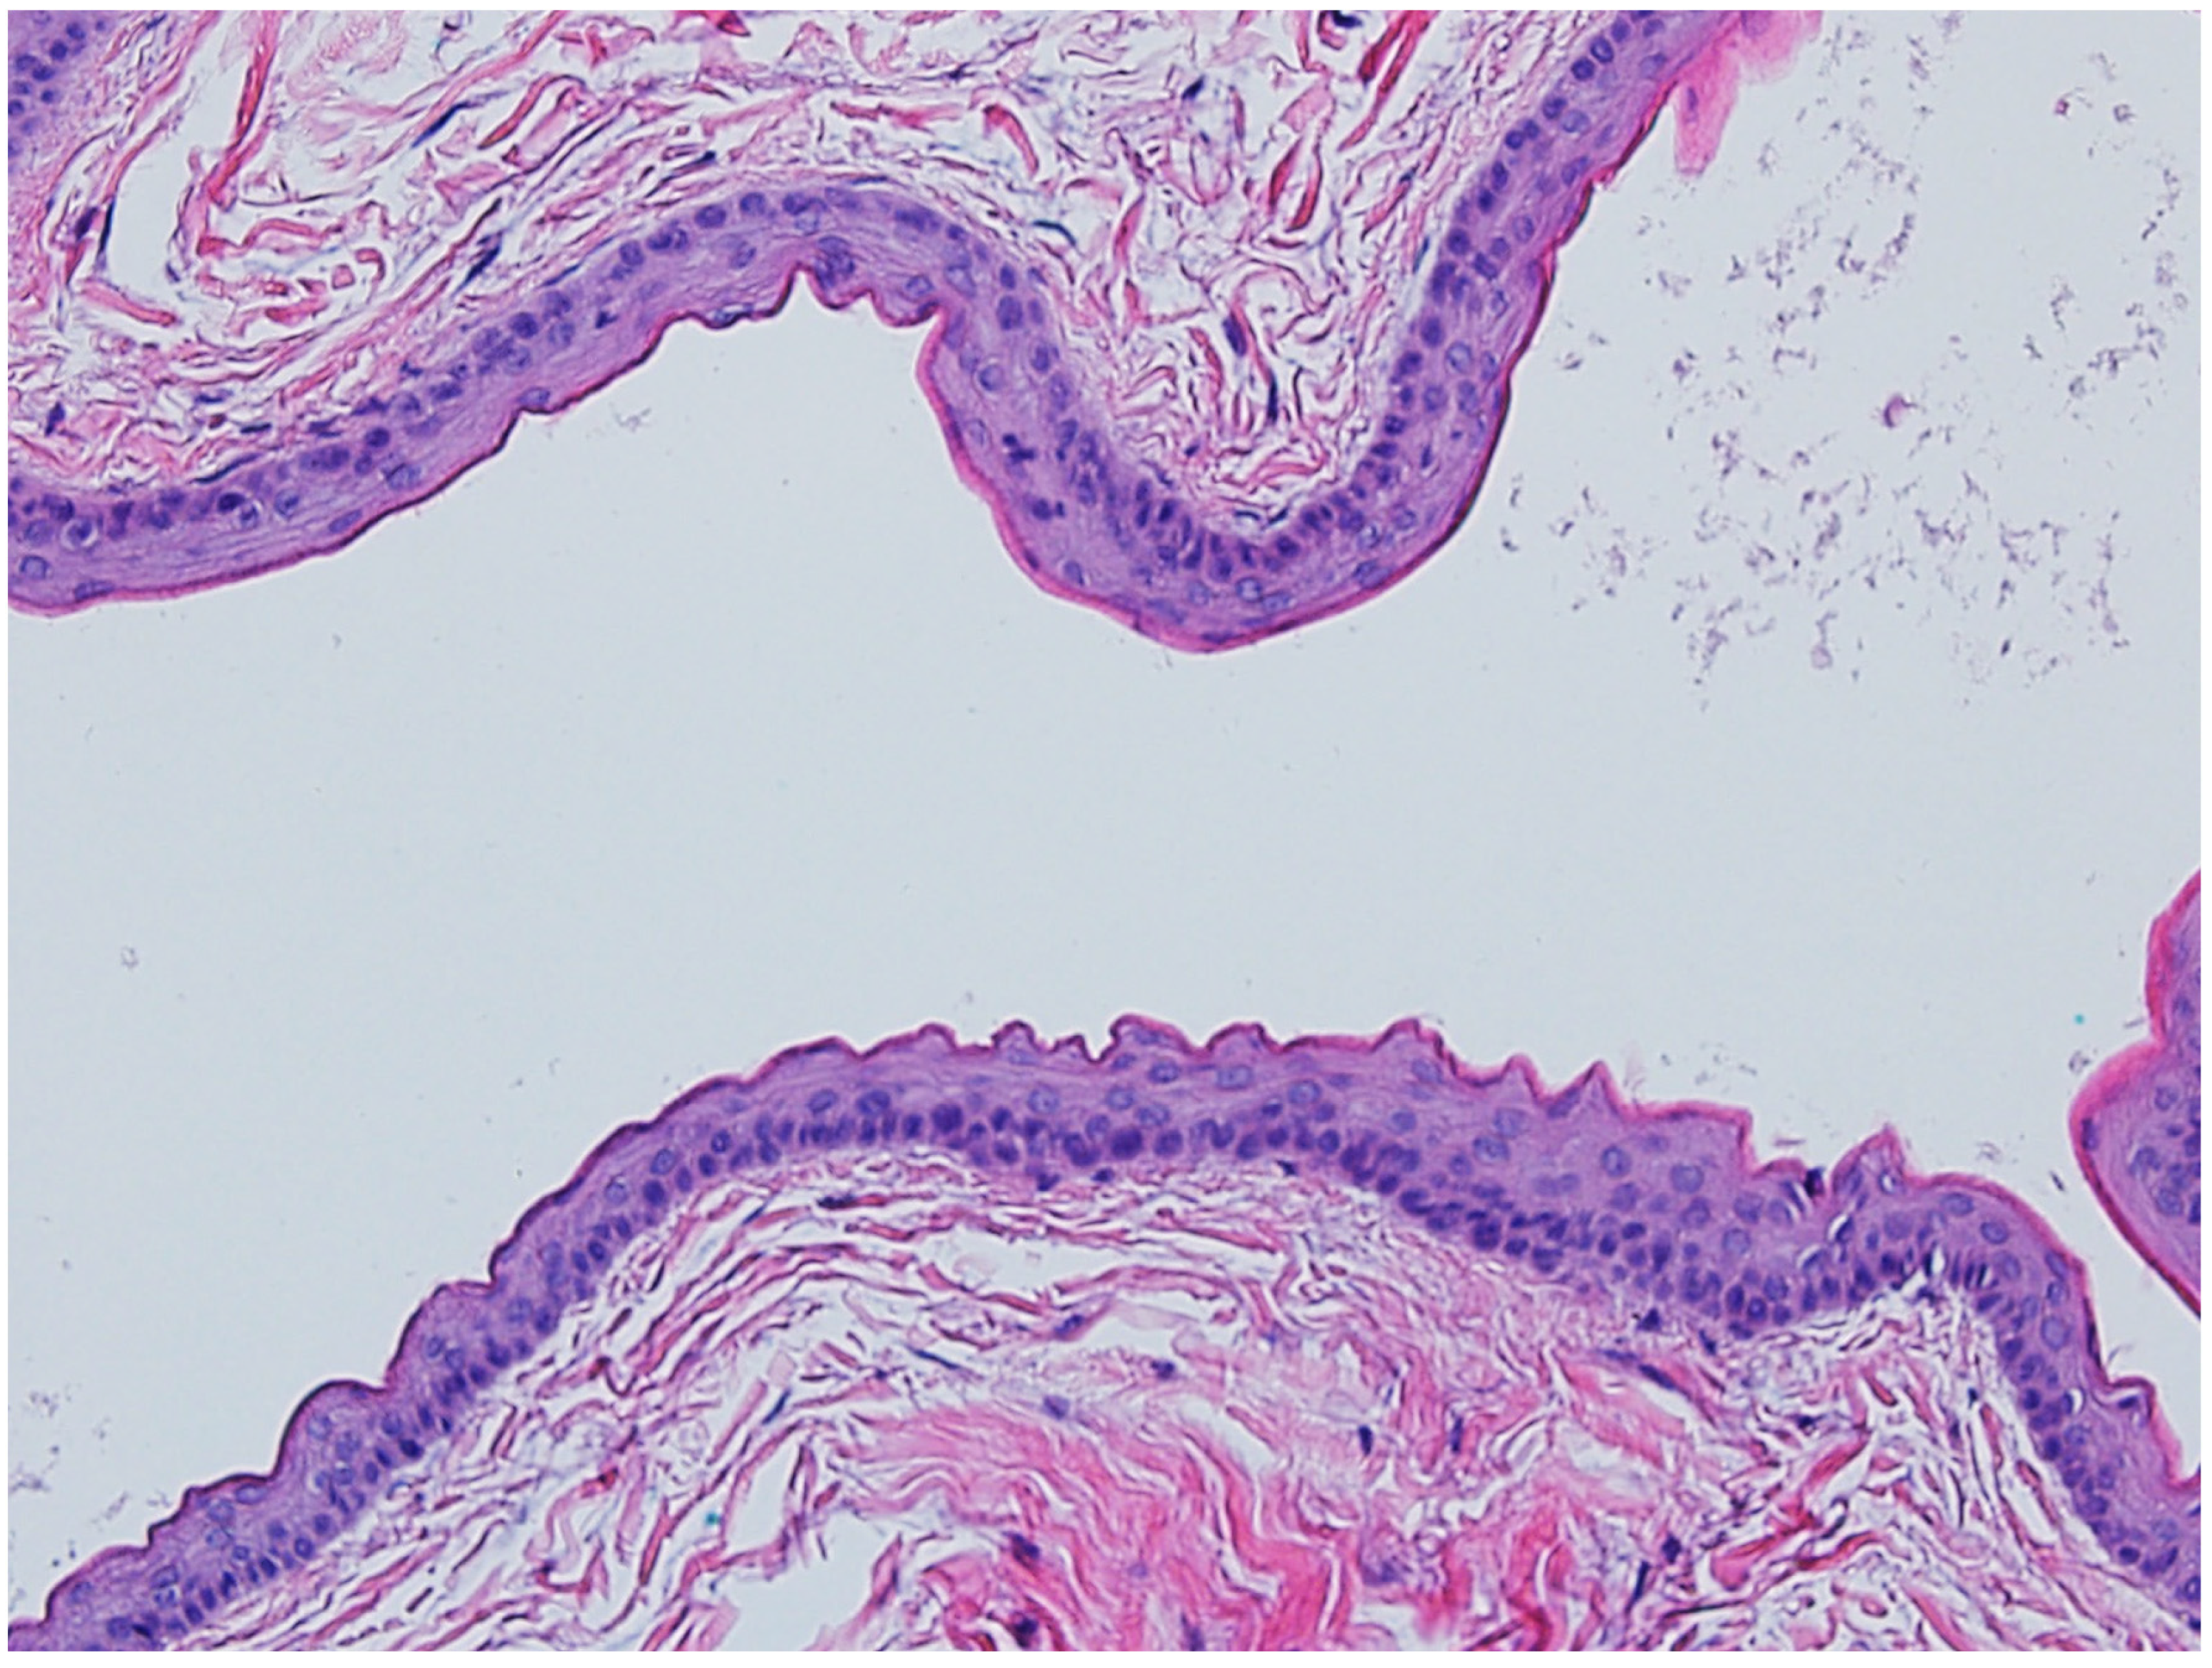

3.2. Steatocystoma